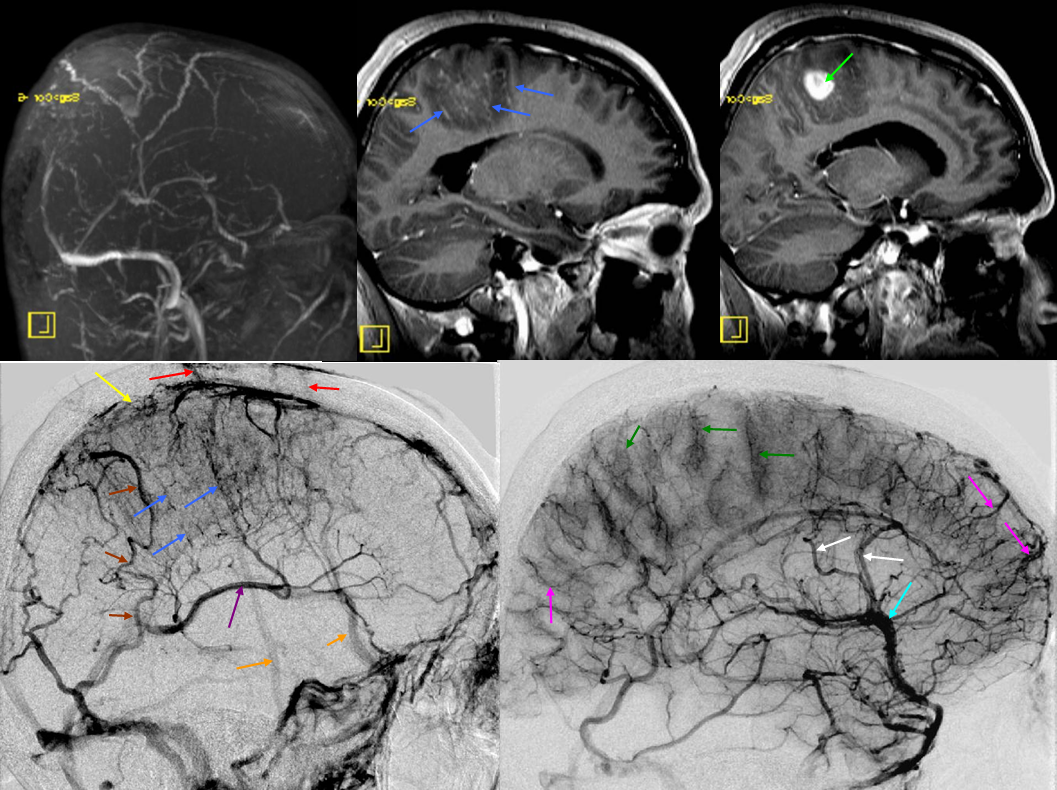

All of the above anatomic knowledge can become very useful in evaluation of venous thrombosis. Numerous collateral pathways develop in this setting attempting to compensate for the loss. The most dramatic cases usually involve the largest channel — the superior sagittal sinus. In this case, a man presented with what initially was thought to be vasculitis-related brain hemorrhage. Subsequent workup led to an angiogram, where sagittal sinus thrombosis with extensive trans-cerebral and trans-osseous emissary vein collateral channels was seen. In retrospect, these findings were present on the patient’s earlier contrast MRI. “Venovibe” or other contrast-enhanced MR venograms can very sensitive, particularly when interpreted with the appropriate index of suspicion. Noncontrast 2-D time of flight MRV I consider to be next to useless as a problem-solving technique. Any thin-slice postcontrast T1 study is vastly superior.